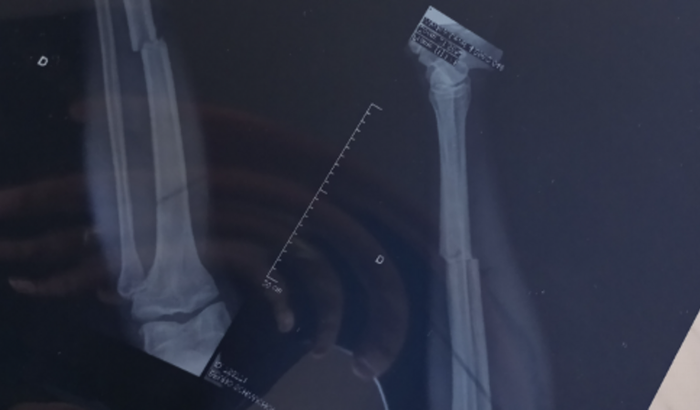

Cirurgia para correção e calcificação óssea "tíbia"

ola pessoal, me chamo Bruno schwuchow Gonçalves e  venho através dessa vaquinha online contar pra vocês um pouco da minha situação. No dia 27 de agosto em uma partida amistosa de futebol, aonde eu jogo a 10 anos já no time do ROMA CANOAS, tive a infelicidade de sofrer uma falta violenta aonde acarretou na fratura da tíbia da perna direita, após raio x no HPSC foi diagnosticado a fratura, tive os primeiros socorros tudo como previsto, então fiquei uma semana somente com a tala pois não teria como por gesso por conta do inchaço da perna, depois de 7 dias retornei em uma consulta com especialista como indicado no HPSC aonde fiz novamente um raio x e a lesão estava do mesmo jeito porém já não estava mais inchado a perna, então foi colocado GESSO, aonde tive a informação do Dr que iria ficar três semanas com a perna totalmente imóvel (GESSO NA PERNA TODA) E APÓS ESSE PERÍODO COLOCARIA OUTRO GESSO SOMENTE DO JOELHO PARA BAIXO. Passadas essas 3 semanas retornei ao consultório aonde realizei novamente um raio x e tive a notícia de que meu osso não estava calcificando, estava muito longe ainda uma parte da outra da tíbia. Foi aonde tive a notícia de que só seria possível a correção da fratura com cirurgia, hoje me encontro já a 33 dias de cama com a perna totalmente imóvel, me movo pouco de muleta somente para coisas essenciais como tomar banho, urinar e higiene. Então através disso hoje eu preciso um valor de R$ 18.000,00 para pode fazer está cirurgia. No momento trabalho de carteira assinada aonde sou motorista, porém eu não tinha convênio médico, e preciso muito voltar ao trabalho e com a cirurgia consigo voltar a minha rotina o quanto antes, hoje me encontro sem renda alguma, fiz a consulta e perícia médica do INSS aonde até hoje estou a espera do resultado. CONTO COM A AJUDA DE TODOS QUE PUDER AJUDAR NESSE MOMENTO, SEI QUE POUCOS SABEM DA MINHA SITUAÇÃO PORQUE NÃO HAVIA NECESSIDADE NO MOMENTO DE ESTAR FALANDO DA MINHA SITUAÇÃO, MAS HOJE VENHO PEDIR A VOCÊS POIS PRECISO DESTE VALOR PARA REALIZAR A CIRURGIA, AGRADEÇO DE CORAÇÃO A TODOS E QUE DEUS POSSA RETRIBUIR EM DOBRO A CADA UM DE VOCÊS. ACREDITO QUE A VAQUINHA TENHA UM VALOR FIXO A SER FEITO ENTÃO QUEM QUISER CONTRIBUIR COM QUALQUER VALOR SIMBÓLICO PODE FAZER VIA PIX TAMBÉM. MEU PIX É CPF    02851544004. NOME: BRUNO SCHWUCHOW GONÇALVES CONTA: CAIXA ECONÔMICA FEDERAL